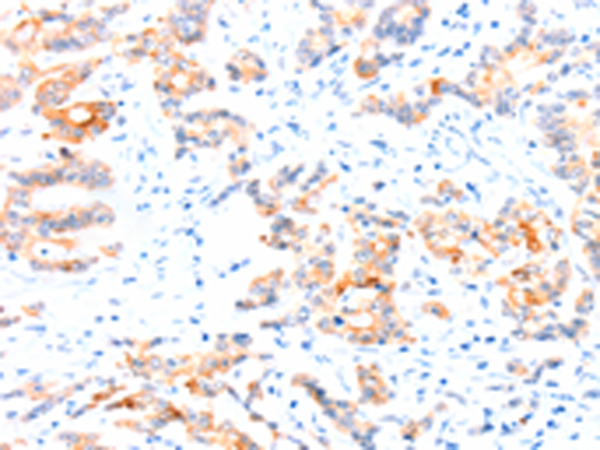

分类: 科研抗体货号: P04685别名: APE; GIV; GRDN; HkRP1; GIRDIN; KIAA1212应用: IHC反应种属: Human, Mouse